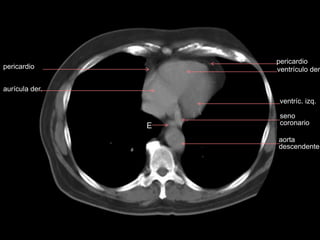

ventrículo der. aurícula izq. v.ácigos aurícula der. aorta descendente ventrículo izq tabique interventric. pericardio

aurícula der. ventrículo der. ventríc.izq. E pericardio pericardio aorta descendente seno coronario